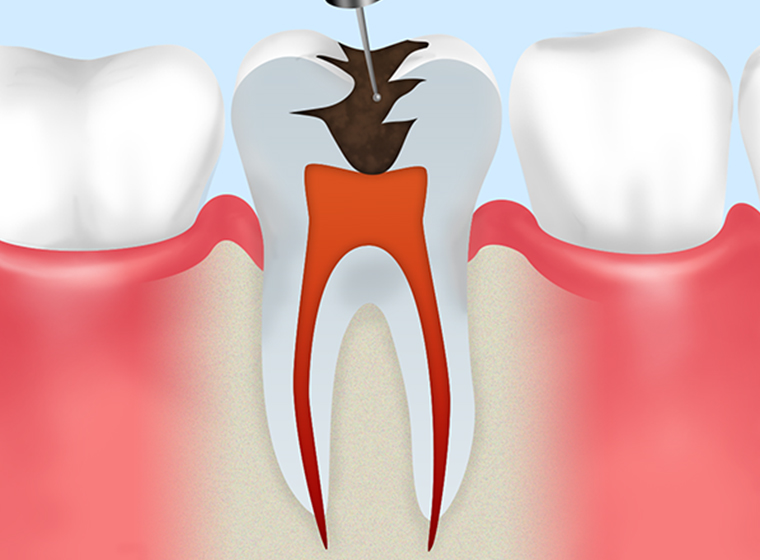

- STEP1

むし歯の除去 -